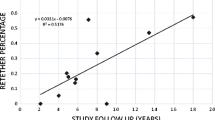

Bowman RM, Mohan A, Ito J, Seibly JM, McLone DG (2009) Tethered cord release: a long-term study in 114 patients. J Neurosurg Pediatr 3:181–187. https://doi.org/10.3171/2008.12.PEDS0874